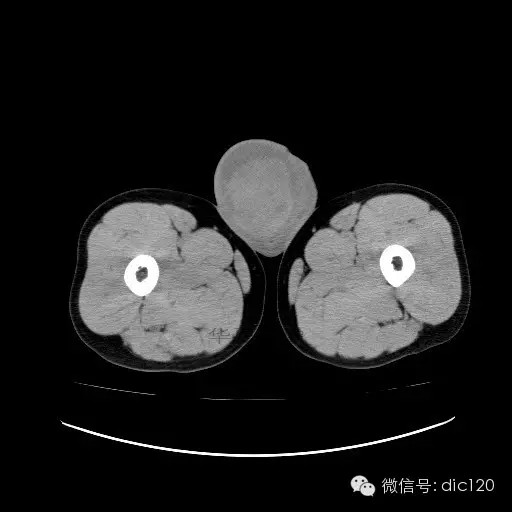

【影像表现】

青年男性,右侧睾丸肿大,边界清晰,增强后睾丸不均匀中度强化,内可见多灶囊变坏死区,动脉期肿块内有细小动脉血管显示,延迟期可见分隔样强化,鞘膜囊可见积液。

定位定性:右侧睾丸恶性肿瘤。

【影像诊断】

右侧睾丸精原细胞瘤,右侧睾丸鞘膜积液。